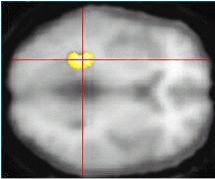

![]() |

The gray scale depicts averaged T1-weighted activity on MR. The color scale represents PET data at all voxels where perceived memory decline and metabolic decline over subsequent years (2) were significantly correlated (p<0.001). Images courtesy of Dr. Gary Small.